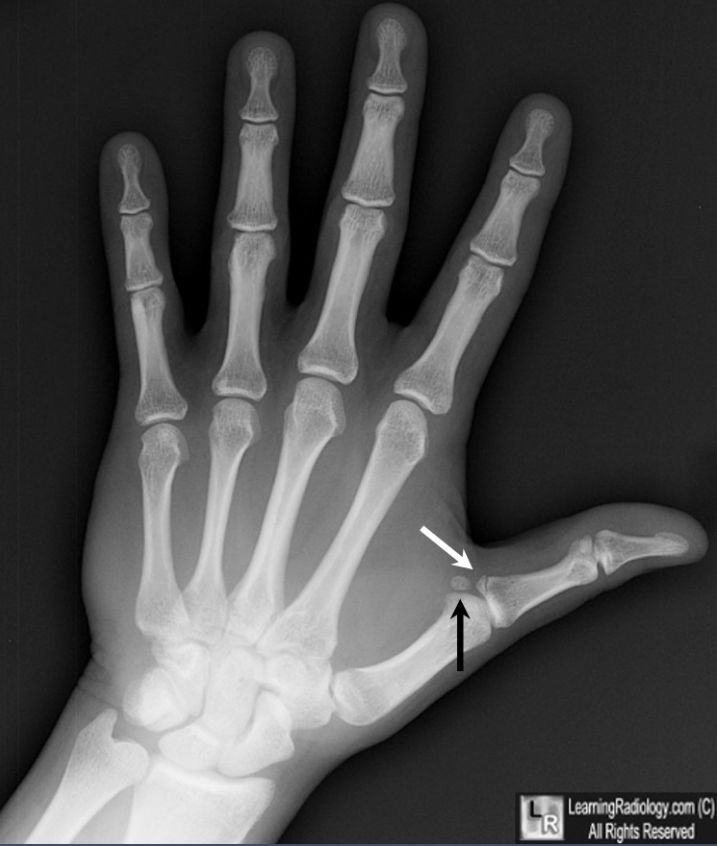

少见单纯拇指掌腕关节脱位

这个x光片看来拇指有脱臼或者骨折吗